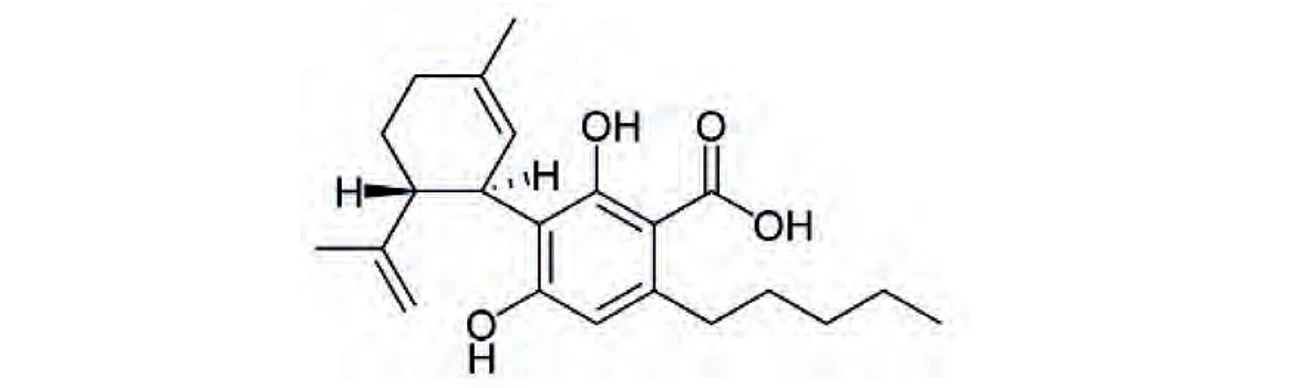

PČR: Kyselina kanabidiolová (CBDA)

PČR: Kyselina kanabidiolová (CBDA)

Biosyntéza (Obr. 5) začíná vytvořením dvou kanabinoidních prekurzorů – geranyldifosfátu a olivetové kyseliny, které spolu kondenzují za účasti geranyltransferasy a vzniku kanabigerolové kyseliny (CBGA). CBGA se následně transformuje na tetrahydrokanabinolovou kyselinu (THCA), kanabidiolovou kyselinu (CBDA) a kanabichromenovou kyselinu (CBCA) pomocí THCA synthasy, CBDA synthasy a CBCA synthasy. Tetrahydrokanabinol (THC), kanabidiol (CBD), kanabigerol (CBG) a kanabichromen (CBC) vznikají dekarboxylací ze svých kyselin během skladování vlivem tepla a světla za uvolnění CO211. THC a iso-THC mohou také vznikat kysele katalyzovanou cyklizací CBD vytvořením příslušných karbokationtů na C-8 a C-1 CBD skeletu (25).

PČR: Obr. 5 – Biosyntéza kanabinoidů a hlavní rozkladné produkty THC (8)

PČR: Obr. 5 – Biosyntéza kanabinoidů a hlavní rozkladné produkty THC (8)